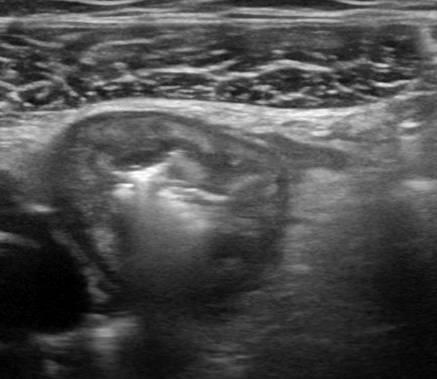

Viêm ruột

» Thông tin: Nữ giới – 18 tuổi.

» Lâm sàng: Tiêu chảy.